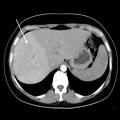

Dumortier J, Ronot M, Beaufrère A. Quand penser à une maladie vasculaire du foie  ?  Rev Prat 2025 ;75(10) :1081 - 5.